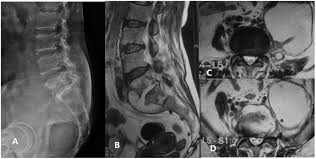

In spite of making rapid strides in healthcare in the last few decades, tuberculosis is still a very common problem in India, Bangladesh, Afghanistan, Pakistan as well as Africa. A bug called Mycobacterium tuberculosis causes TB. Bone TB is the next most common site after lungs. Amongst bones, it is the spine (neck and back) that is the most common site of tuberculosis. Tuberculosis can strike anyone at any age and there may be no specific predisposing factor in most patients. Children and elderly; people with decreased immunity; family history or past history of tuberculosis and patients who have had contact with a known case of tuberculosis are some groups that are prone to developing tuberculosis. Tuberculosis can affect any part of the spine from the upper neck to the tailbone.

Patients with tuberculosis of any part of the spine may complain of pain localized to that area, fever (especially in the evenings), weight loss, loss of appetite and a generalized feeling of being unwell. Their pain may be especially worse at night or during rest. Tuberculosis of the spinal bones can easily spread to the spinal cord resulting in weakness and numbness of extremities, paralysis and alteration of urine and motion pattern. It is this proximity to the spinal cord that makes TB spine a problem that cannot be taken lightly.